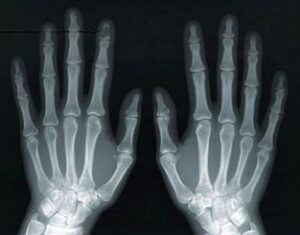

The service supports residents with a suspected fracture to an upper or lower limb (shoulder to hand, knee to foot), or where a chest X-ray is clinically indicated – in situations where the resident would previously have been taken to hospital for imaging. It is intended for residents who are clinically stable, where there is no immediate need for emergency intervention and where it is safe and appropriate for assessment to take place within the care home setting following discussion with FNC+Plus.